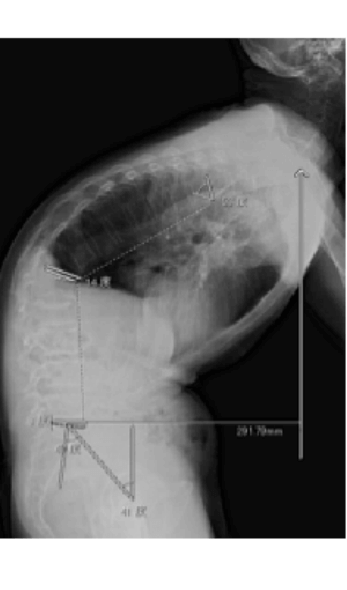

3Dテンプレートシミュレーション・Navigation system

THAは股関節疾患の末期像に対して行われる手術法で、関節面の不良な部分を除去し、人工関節に置き換える術式です。寛骨臼側の人工関節はカップまたはソケット、大腿骨の方をステムと呼びます。骨と人工関節の描着には骨セメントを使用する場合としない場合があり、後者をセメントレスと言い、当科の初回THAは大部分を占めます。摺動面における摩耗を減少させるため、ポリエチレン、セラミックや金属などの材料が改良されています。THAにおいては正確なカップやステムの設置が重要ですが、当科では3Dテンプレートによるコンピュータシミュレーションの術前計画と術中にはNavigation systemをすべての手術に使用し、精度を挙げています。